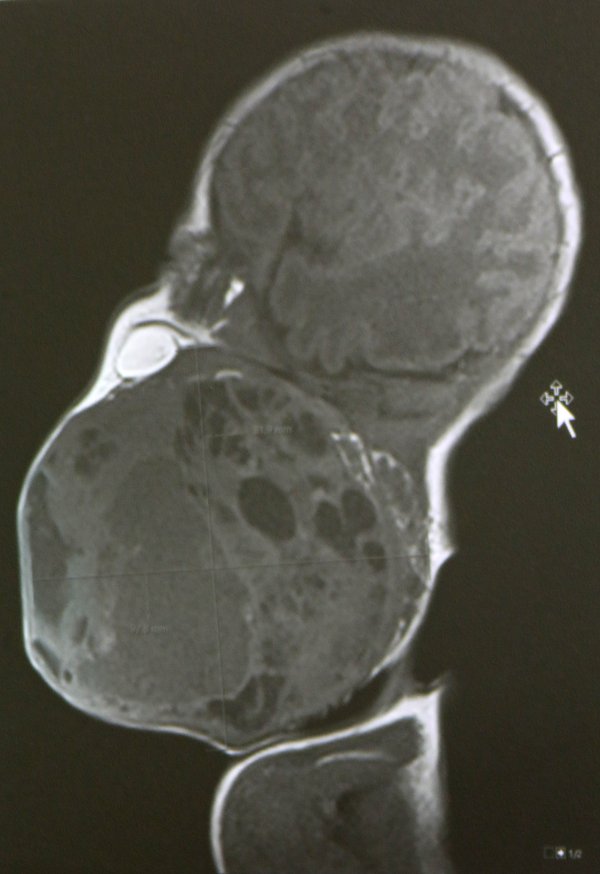

Prema nalazima magnetske rezonance prije poroda, tumor je bio gotovo veličine djetetove glave i zatvarao je dišne puteve. Dijete bi bilo životno ugroženo ako bi se rodilo normalnim putem, stoga je tim liječnika morao razraditi i biti spreman na nekoliko varijanti liječenja, a na kraju je profunkcionirala prva opcija.